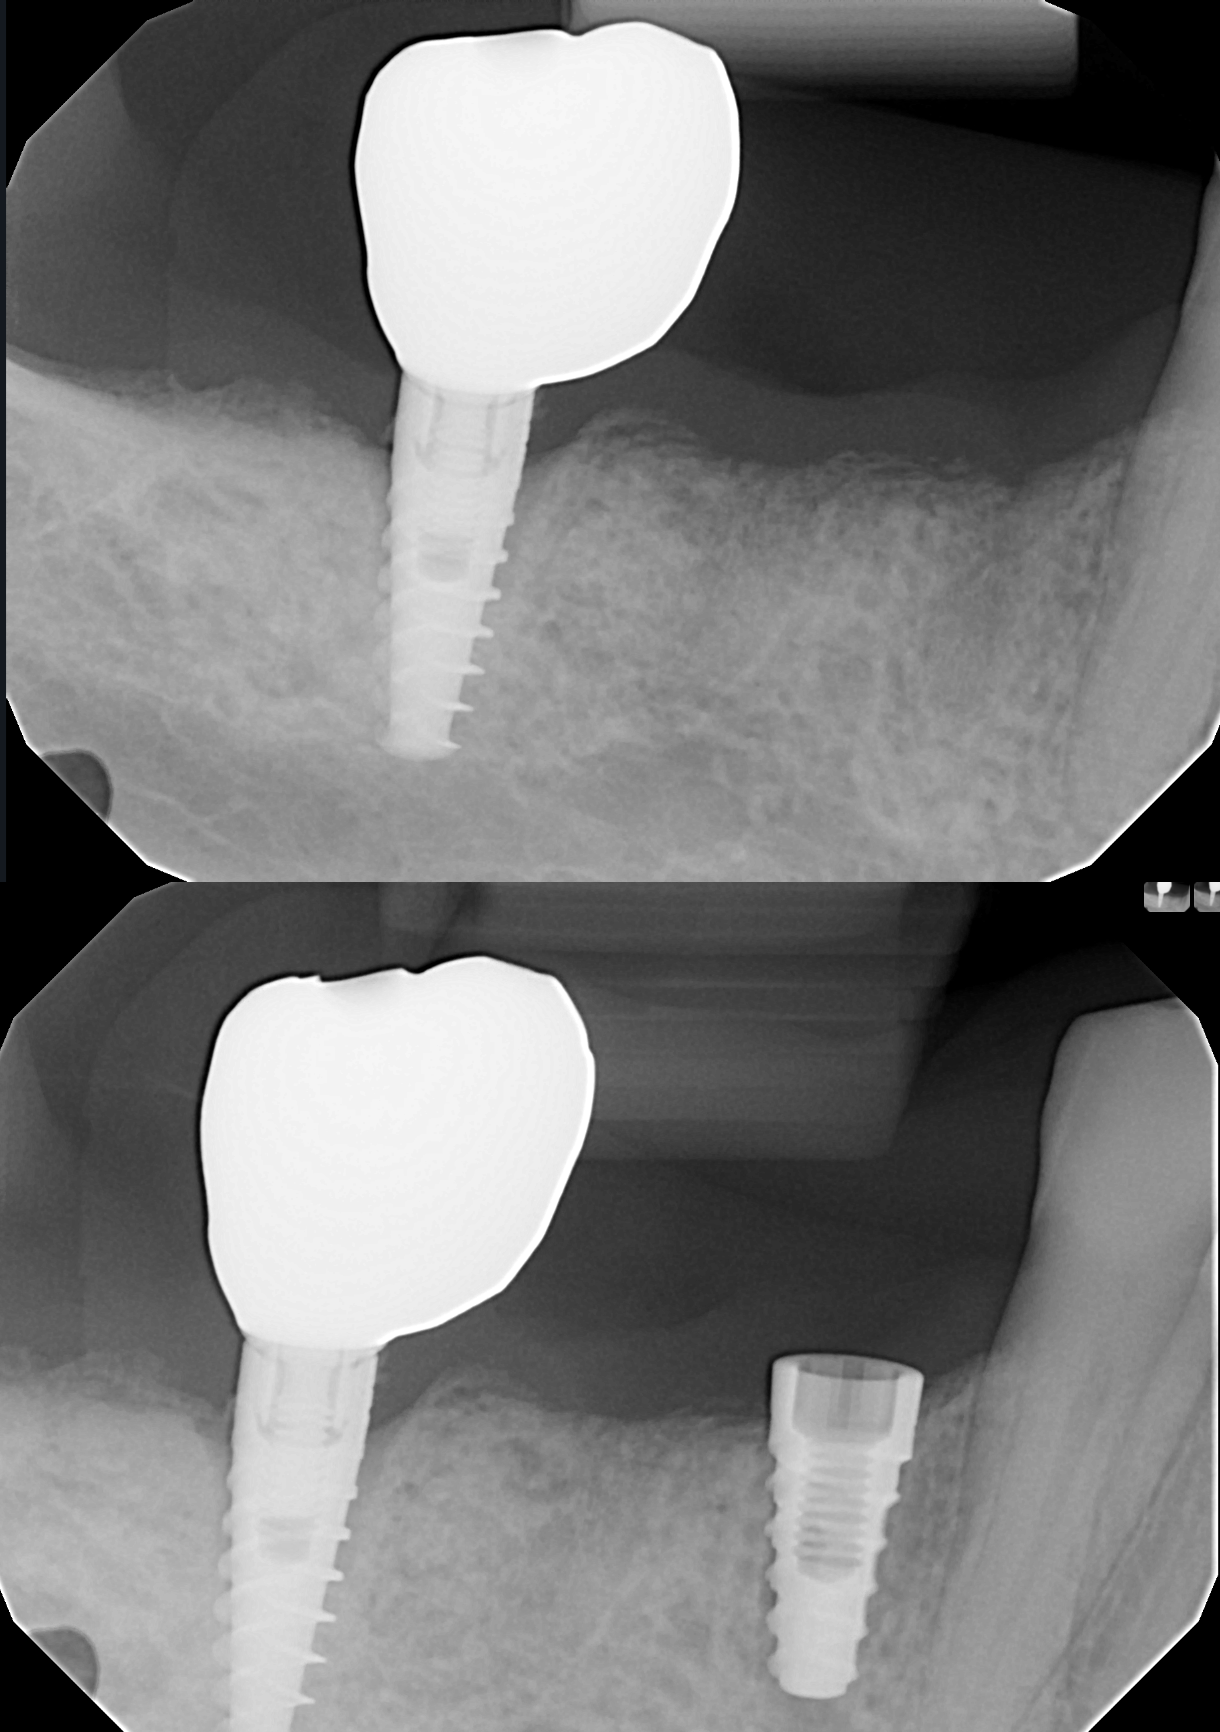

A selection of before and after X-ray images from cases I have performed, showcasing single implants placed in posterior gaps and single-tooth spaces. This is often the ideal solution in these situations.